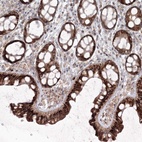

Immunohistochemical staining of human colon shows strong cytoplasmic positivity in glandular cells.